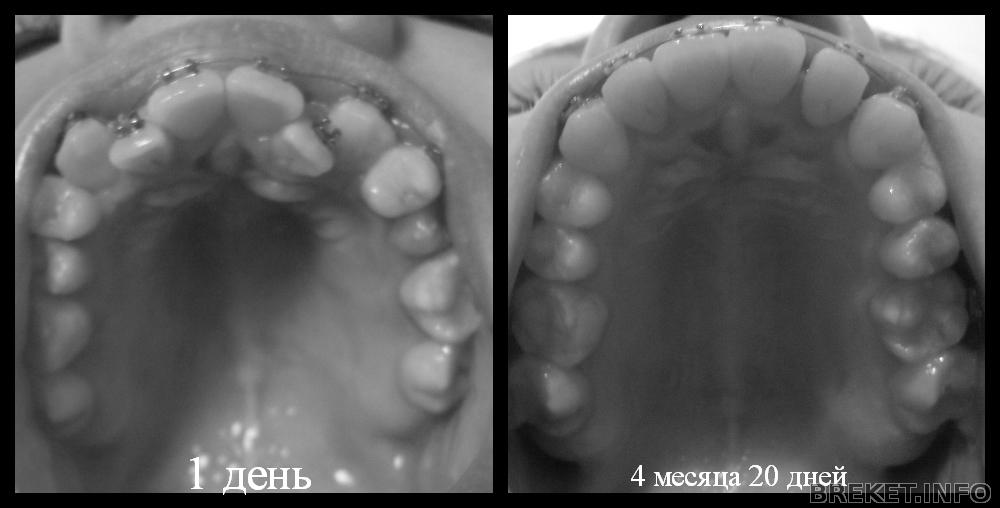

Наконец-то собралась с мыслями ,сфоткала свои зубки и пишу очередной пост,точнее заметку.

Итак,нам ВЧ 4 месяца 20 дней (на момент фотографирования),сейчас уже 21 день)

НЧ 1 месяц 28 дней

Поймала себя на мысли,что смотрю свои старые фотки и такое ощущение,что там не мои зубки,они такие ужааасные!!!

Из плохого:стала челюсть кривая и наклон верхних зубов меня пугает((

4месяца20дней.jpg

4_mesyaca_20_dney.jpg